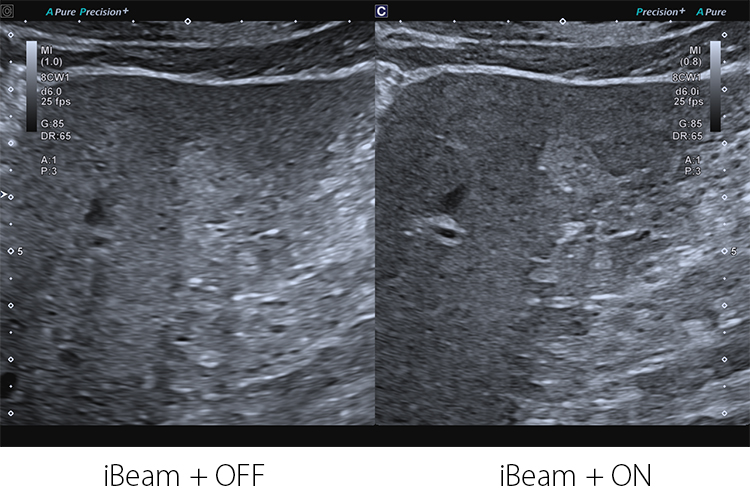

Aplio beyond sử dụng công nghệ iBeam+ và chế độ Precision+ Fine Processing giúp nâng cao chất lượng hình ảnh bằng cách giảm nhiễu, tăng độ phân giải và cải thiện độ đồng nhất hình ảnh. Điều này mang lại hình ảnh mượt mà, đường nét rõ ràng và chi tiết lâm sàng sắc nét ở nhiều ứng dụng khác nhau, từ siêu âm tổng quát đến các thủ thuật chuyên sâu.